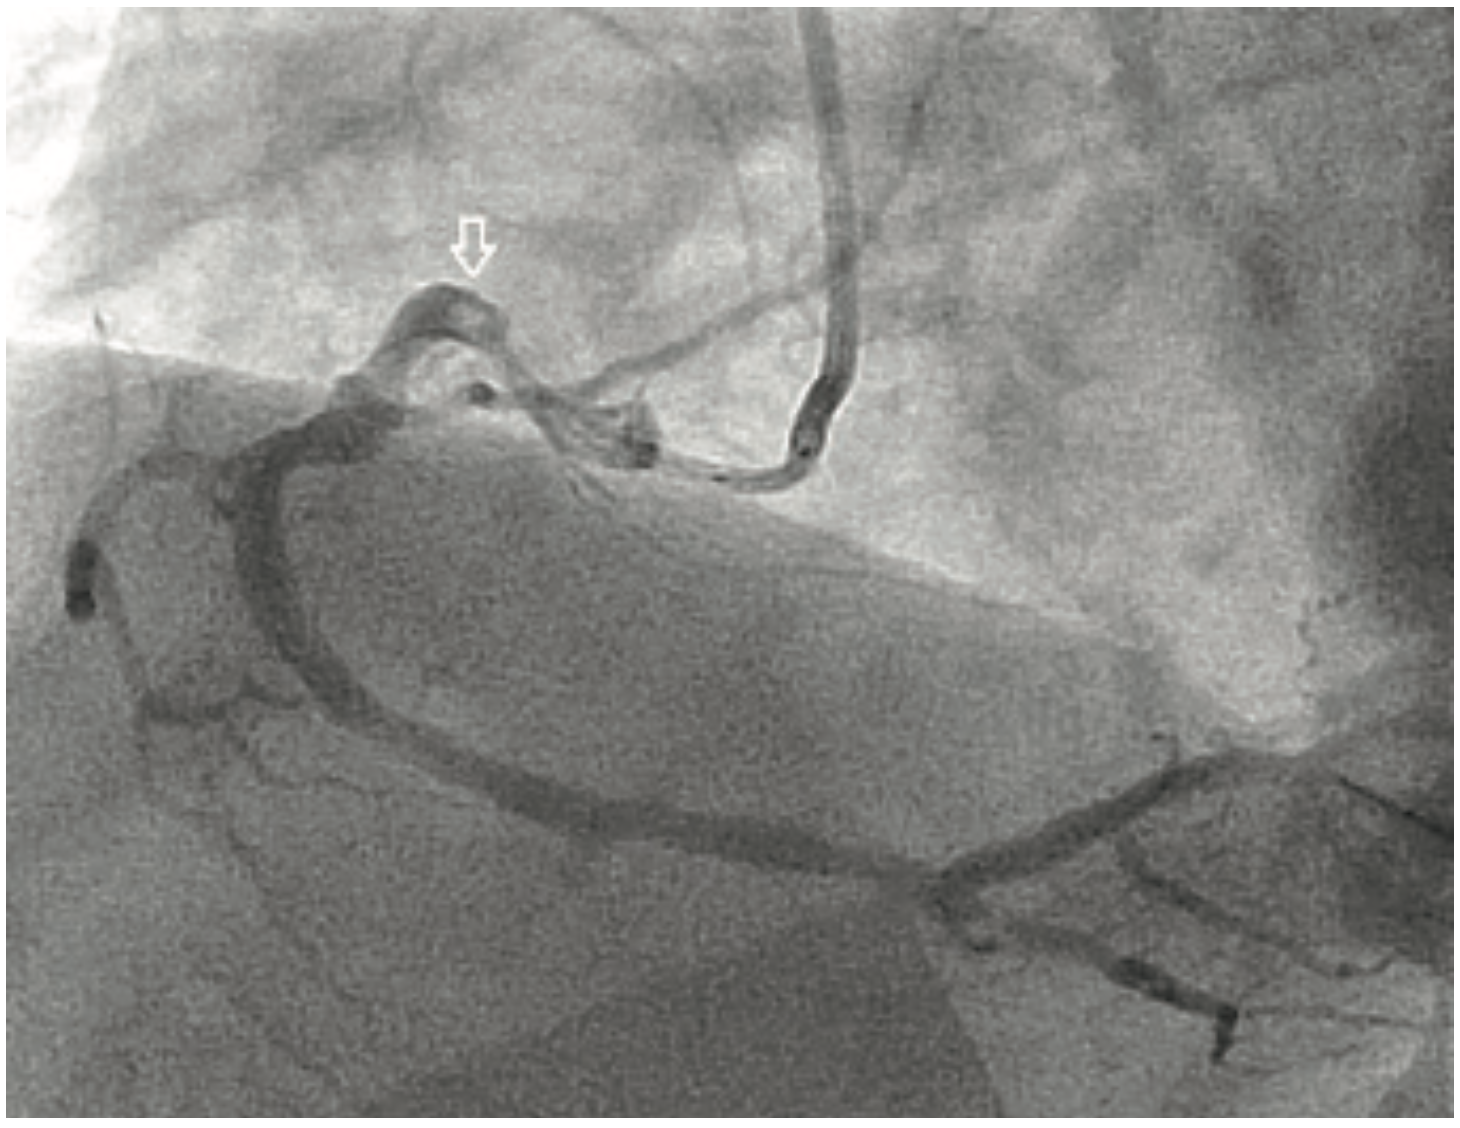

A 70-year-old male without prior cardiac history presented with new-onset angina and a non ST-elevation myocardial infarction (NSTEMI). Angiography showed subtotal occlusion of a proximal right coronary artery (RCA) with a large thrombus burden and Thrombolysis in Myocardial Infarction (TIMI) 2 flow (Figure 1). A 6 French (Fr) Amplatz left (AL) 0.75 catheter and a 6 Fr GuideLiner were selected for support with a Balanced Middleweight (BMW) coronary wire (Abbott Vascular). The GuideLiner was carefully advanced to the proximal part of thrombus and aspiration with a 50 cc syringe via a Y connector through the side port was performed with partial success. Next, a compliant balloon (Trek Rx 2.0 x 12 mm [Abbott Vascular]) was inflated to 18 atmospheres (atm) at the site of the stenosis/thrombus. Another aspiration attempt through the GuideLiner was successful. A Resolute stent (3.5 x 18 mm) (Medtronic) was deployed at 22 atm with good expansion. A follow-up angiogram (Figure 2) after aspiration thrombectomy and stent deployment revealed TIMI-3 flow with no evidence of the thrombus and good distal flow. The patient was started on optimal medical therapy, including continuation of a glycoprotein (GP) IIb/IIIa inhibitor. The patient did well post PCI and was discharged the next day in stable condition.